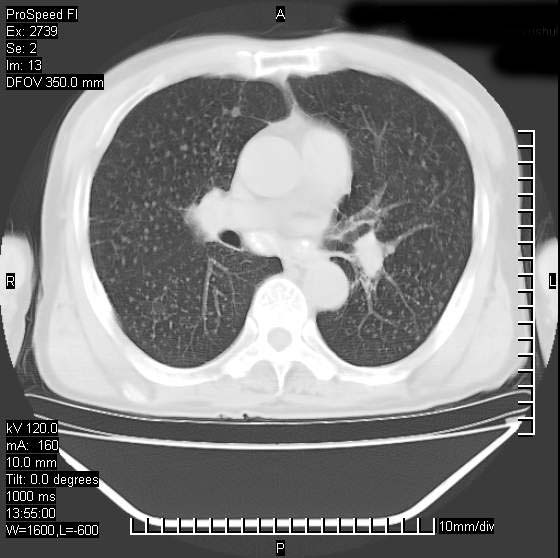

以下是引用andymaomao在2007-12-7 15:54:00的发言:[br]1.双上肺陈旧肺tb灶;[br]2.双中上肺矽肺;[br]3.双肺气肿;[br]4.图中箭头所指乃下腔静脉。

以下是引用山之魂海之韵在2007-12-7 18:59:00的发言:[br]支持矽肺,左肺上叶陈旧性结核,肺气肿。箭头所指乃下腔静脉。下腔静脉显影比主动脉显影迟,增强动脉后迟可以是不均匀的。

以下是引用chengjiaqiu1在2007-12-7 17:49:00的发言:[br]矽肺,左肺上叶陈旧性结核,肺气肿。中箭头所指乃下腔静脉。